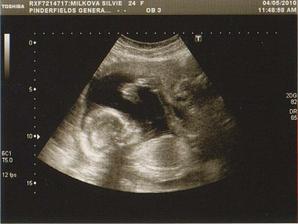

dnes jsme dostali výsledek z NT screaningu! Je to 1:100000 🙂)))